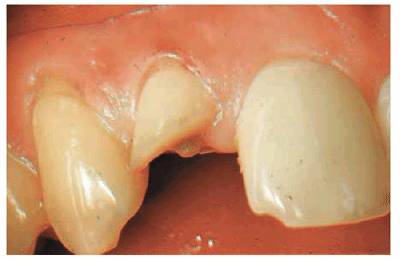

Figure 19-37A: View of maxillary central incisors following excavation of extensive caries. The pulps were not exposed.

Figure 19-37B: Radiograph of the same teeth. Note the minimal thickness of dentin adjacent to the pulp chambers.

Figure 19-37C: Root canal therapy completed on the maxillary central incisors.